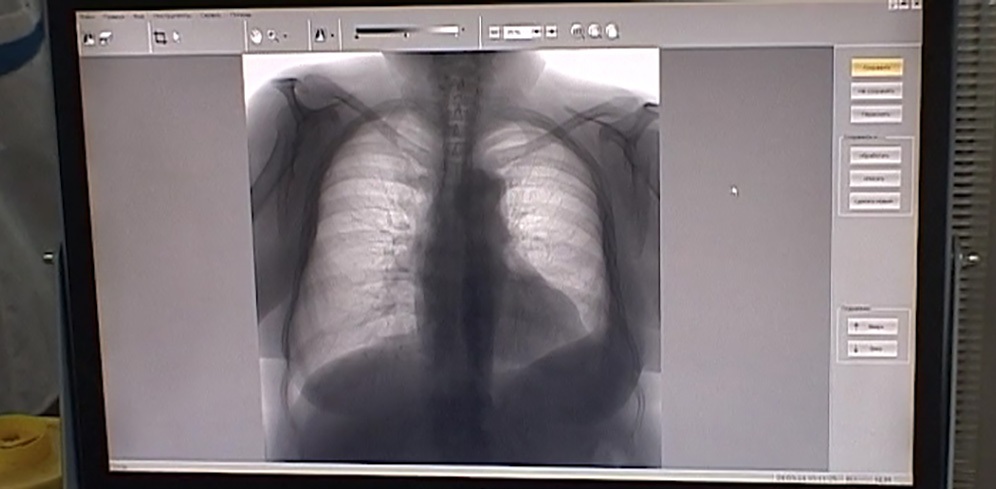

Костромская область обновила оборудование для диагностики туберкулеза

Костромская область приобрела аппарат УЗИ для противотуберкулезного диспансера, что позволит повысить качество диагностики и лечения.

На приобретение нового аппарата УЗИ направлено более 4 млн. руб. Медики отмечают, что он незаменим для обследования пациентов после проведения туберкулезной терапии. Он позволяет получить более четкую визуализацию и упрощает оценку результатов исследований. Это помогает более точно оценить воздействие лечения и скорректировать его в случае необходимости.

Екатерина Борисова, врио главного врача Костромского противотуберкулезного диспансера: «Каждый пациент до лечения и в процессе лечения может до 5-6 раз проходить ультразвуковое исследование, если это необходимо. Новое оборудование позволит улучшить диагностику больных туберкулезом, тем самым повысит эффективность лечения туберкулезных больных».